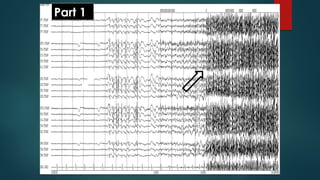

Part 1

Part 2

• #142ย Generalized tonic-clonic seizure (Part 1). Onset of generalized tonic-clonic seizure, longitudinal average ear referential montage. Generalized spike and wave and polyspikes noted at seizure onset (filled arrow), evolving to continuous activation during tonic phase (open arrow). Copyright 2013. Mayo Foundation for Medical Education and Research. All rights reserved. Courtesy of Dr. Jeffrey W. Britton, MD.